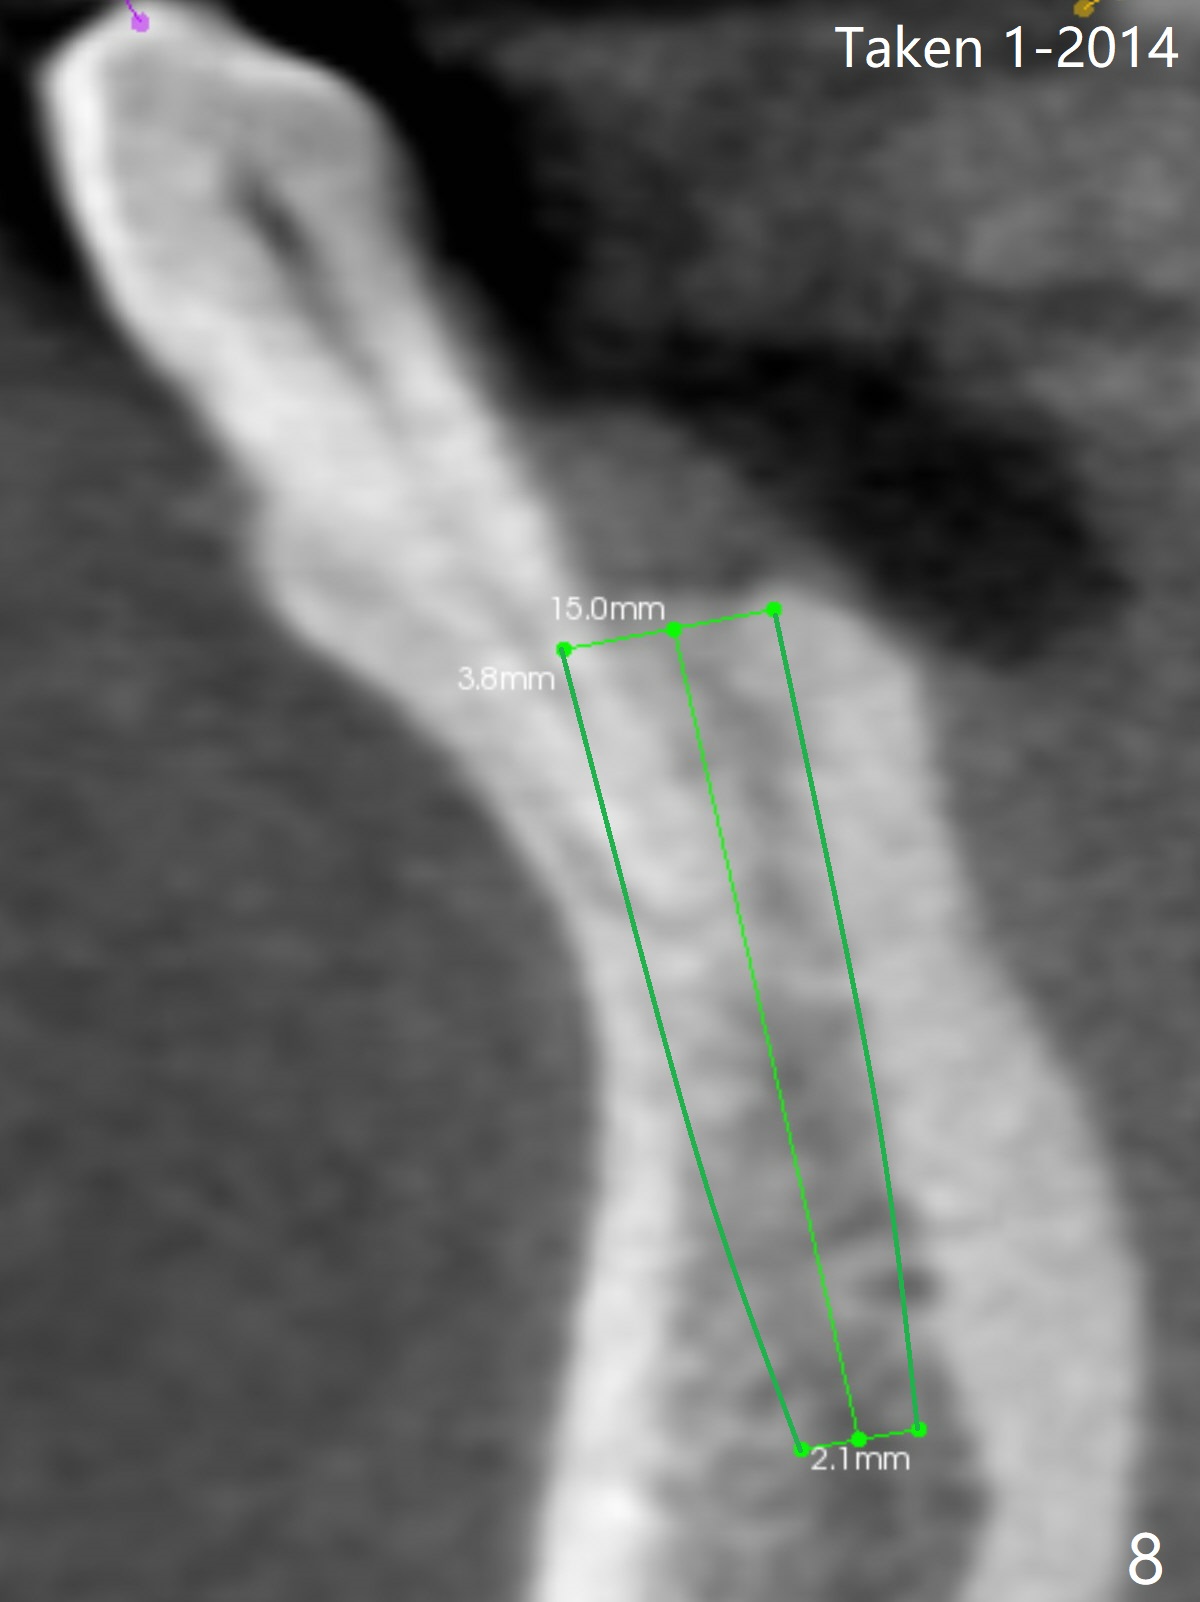

A 44-year-old woman will return for #22/23 (fusion) extraction and implant 2.5 months after one at #25 (Fig.1). If the mesiodistal width of the extraction socket(s) is not particularly wide, one implant will be placed. The tooth #22 seems to be buccally positioned (Fig.2 B). After extraction (Fig.3 black area), initiate osteotomy lingually (red line). Since the spongy bone is not wide buccolingually, a 3 mm implant appears to be appropriate (Fig.4).